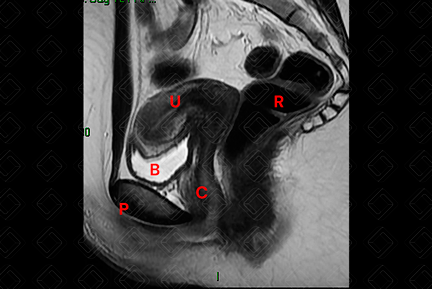

O protocolo básico da RM de pelve consiste em: T1 axial, T2 nos três planos (coronal, sagital e axial), T1 com saturação de gordura pré e T1 com saturação de gordura pós-contraste (Figuras 1, 2 e 3).

Texto alternativo para a imagem Figura 3. RM de pelve feminina, ponderada em T2, plano sagital. Créditos: Dra. Elazir Mota - Rio de Janeiro/RJ

Legenda das siglas (Figura 3): B = bexiga; C = canal vaginal; P = púbis; R = reto; [cms-watermark] U = útero.